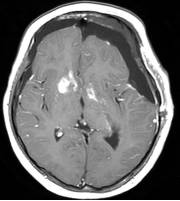

病例二:患儿女性,7岁,主因头痛2年,精神差1个月收入院。入院时头CT见典型的“超大型”颅咽管瘤,直径约9厘米,见图6。

图6.CT显示囊性颅咽管瘤

白色三角显示肿瘤边界